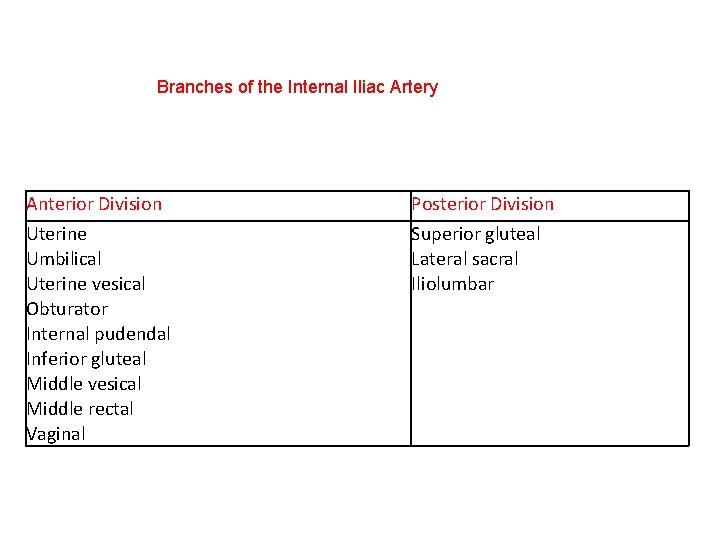

Branches of the Internal Iliac Artery Anterior Division Posterior Division Uterine Umbilical Uterine vesical Obturator Internal pudendal Inferior gluteal Middle vesical Middle rectal Vaginal Superior gluteal Lateral sacral Iliolumbar